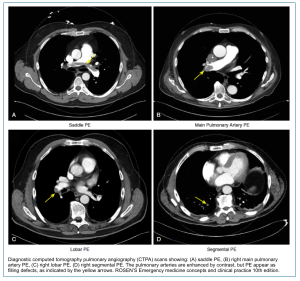

Diagnosis of acute PE on CTPA

The diagnosis of acute pulmonary embolism (PE) on CT pulmonary angiography (CTPA) rests on recognition of a well-defined intraluminal filling defect within the pulmonary arteries. Interpretation requires careful attention to technical quality and multiplanar review to avoid pitfalls *.

Key radiological findings of acute PE in CTPA

Direct Radiologic Signs of Clot

A. Clot appearance and characteristics

◾️Filling defect

- Appears as a low-attenuation area in a contrast-enhanced pulmonary artery.

- Should be visible in more than one plane and across several slices, with sharp borders to distinguish from flow artifact.

- Filling defects in acute PE may be non-occlusive (i.e., partially occlude the vessel) or occlusive (completely occlude the vessel).

- Non-occlusive filling defects. These filling defects can be located within the center of the involved vessel or, less commonly, adherent to the vessel (eccentric).

- Central. Most filling defects are central within the vessel lumen, surrounded by contrast, producing:

- Polo mint appearance: A central filling defect (the clot) surrounded by a rim of contrast within a circular cross-section of the pulmonary artery → looks like a polo mint in axial CTPA (Figure 1.A).

- Tram-track / railway sign: Endoluminal clot is surrounded by a rim of contrast on both sides (in coronal CTPA). Figure 1. B

- Eccentric (i.e., peripheral filling defects). Less commonly, in acute PE, the clot can be located in contact with the vessel wall. Typically, this clot forms an acute angle with the vessel wall (Figure 2).

- Note that in chronic thromboembolic disease, this angle is obtuse (see below for more information).

- Occlusive filling defects

- Occlusive PE prevents opacification of the entire lumen and may distend the vessel (Figure 3).

- Note that occlusive defects are nonspecific for acute PE and may occur in chronic thrombosis as well.

- Keep in mind that non-occlusive but flow-limiting PE can also reduce regional pulmonary blood volume.

B. Pulmonary Artery

The pulmonary artery containing an acute PE will be normal in size or expanded, compared to adjacent patent arteries, due to acute distension (Figure 3).